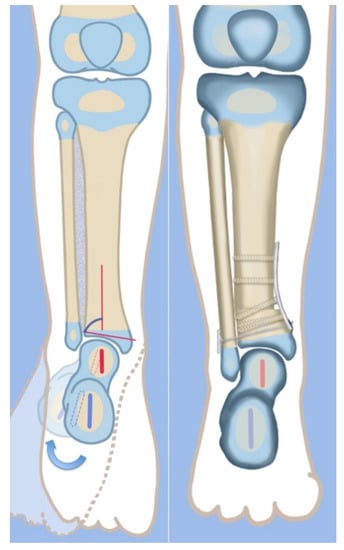

Figure 4.

Illustrations before (left) and after (right) the SHORDT procedure (SHortening Osteotomy Realignment Distal Tibia) for dynamic valgus deformity of Paley type 2 FH. The main elements are the shortening and varusization of the tibial plafond relative to the fibula which does not change length. This eliminates the valgus instability of the ankle joint.